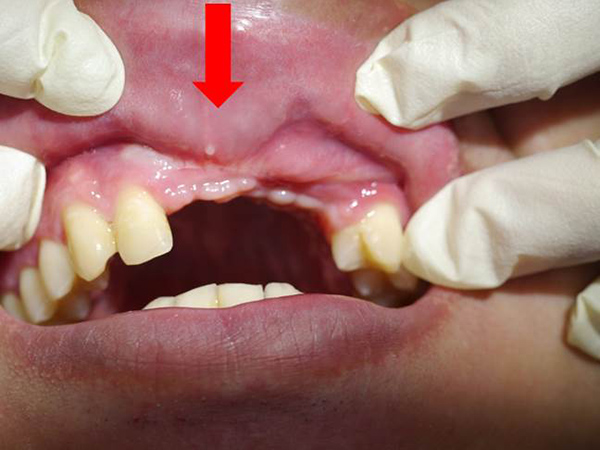

▸ 車禍後,前庭加深手術合併疤痕組織移除+游離牙齦移植覆蓋+雷射輔助修復正常組織案例

| 治療前(紅色箭頭) : 嚴重疤痕組織增生,導致牙齦組織攣縮,嘴唇無法正常閉合,刷牙不舒服,也無法製作正式假牙。 ![]() |

治療後(黃色箭頭) : 前庭恢復正常位置,嘴唇得以正常閉合,疤痕組織移除後,可見新生血管組織,可正常刷牙並製作正式假牙。 ![]() |